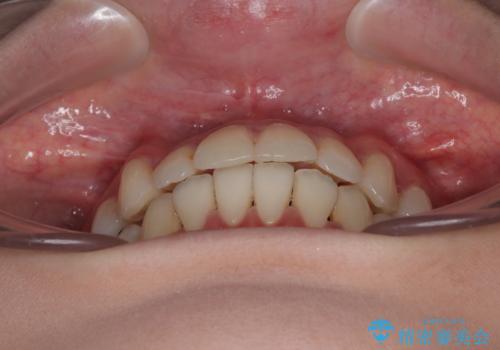

【モニター】前歯のデコボコをインビザラインで綺麗に

- 上下前歯のデコボコとクロスバイトを気にして来院された患者様です。

治療済みの処置歯が多いため、インビザラインを用いて矯正治療を行うこととしました。

下顎臼歯部にブリッジが装着されており、移動不可のため、IPR(歯と歯の間を削る)と歯列全体を拡大させることで、歯並びを整えていくこととしました。

インビザライン特有の奥歯の噛みにくさが治療後半に発現しましたが、無事に終了させることができました。